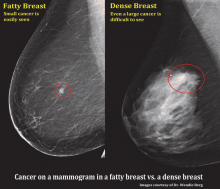

There has been much talk in the news lately about mammographic breast density, its association with the risk of breast cancer and legislative efforts to mandate reporting it to patients. This article addresses the reasons why breast density has become such a hot-button issue and what we might expect from this topic going forward.